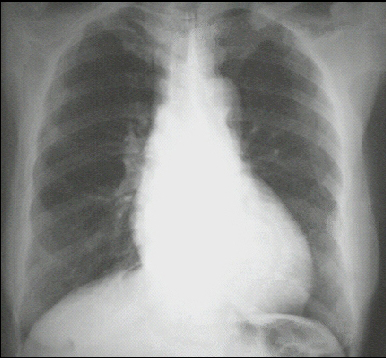

PA view

The PA view demonstrates cardiomegaly, as evidenced by a cardiothoracic ratio greater than 50%. Note also the increased inferolateral cardiac border that is consistent with ventricular enlargement due to volume overload. The ascending, transverse, and descending aortic shadows are also prominent. The lateral view shows left ventricular enlargement, as evidenced by posterior displacement of the left ventricular shadow.